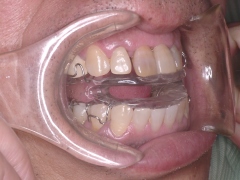

睡眠時無呼吸症侯群

口腔内装置

口腔内装置です

口腔内装置装着中(かなり改善しました)